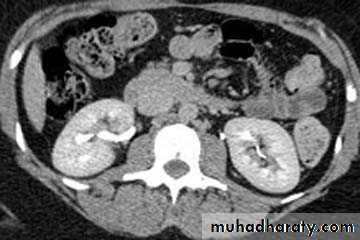

ADPKD:

• Familial disorder

• Age (35-55 years)

• Presented with HTN, renal failure and hematuria.

• Bilateral disease.

• Cysts may also be seen in other organs like liver and pancreas .